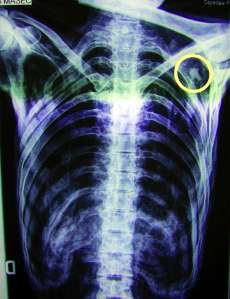

As research continued on the body more discoveries were made. An X-ray examination in 2001 showed that an arrowhead was lodged in the Iceman’s left shoulder. It had hit a main artery and he probably bled to death within minutes. However, the man had also been suffering from many other infections. In 2007 researchers discovered that his body had been infested with whipworm and he was suffering from arthritis. A 2012 study of the body revealed that he was also infected with Lyme Disease. Before dying he had taken a medicinal herb called hop hornbeam suggesting that he may have been suffering from nausea or stomach upset.